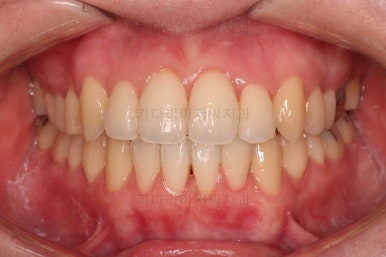

1년 2개월이라는 비교적 짧은 기간안에 원하시는 부분을 깔끔하게 개선했습니다.

전후 비교해 볼게요.

이번 환자분도 삐뚤한 치열을 비발치로,심지어 미니스크류 사용도 없었고 치간삭제도 거의 하지 않았는데요.

입이 나오거나 뻐뜨러지는 느낌 전혀 없죠?

진료 메카니즘을 잘 구성하고 철사를 잘 다뤄주면 좋은 결과를 얻을 수 있답니다.

이상 비발치로 덧니를 개선한 치료사례였습니다.